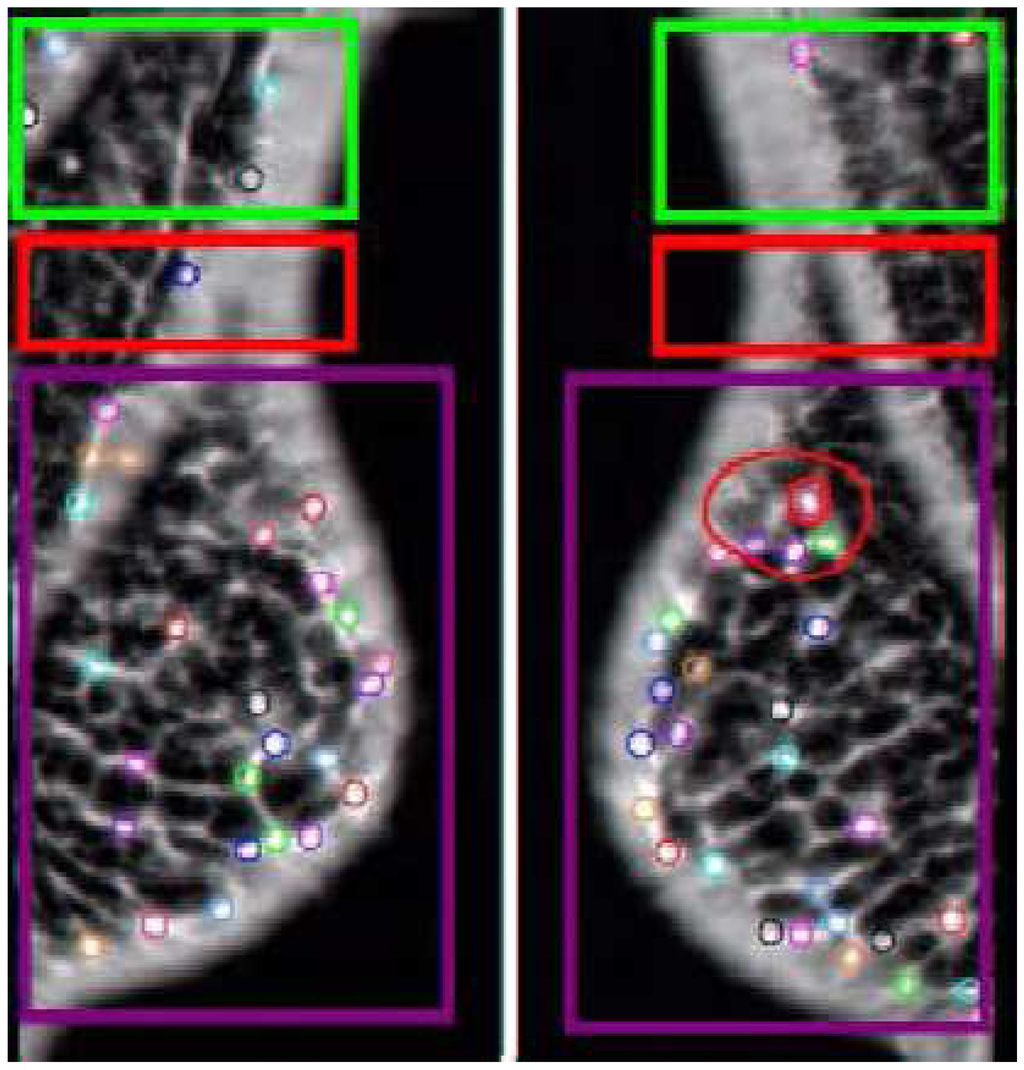

Figure 6. Example Comparison. The AFUM features are the small circles. The automatically created hyper-volumes in this example are the large boxy shapes containing the points, but the same effect can be created with two separators. This case was correctly diagnosed by both the space-based and data-based techniques. Note the red hyper-cluster, which was found to be a significant area in the determination of cancer. In noisy, cancer-free images this area would pick up a statistically equal number of features.

These alternate definitions of clustering focus on increasing the flexibility of the clustering or on decreasing the required number of parameters. An alternate clustering is shown in Figure 7 where the cluster is designed to avoid a noisy area on the images. The focus on decreasing the number of parameters is required to improve the generalizability of the technique when using supervised learning, which is another adaptation we did to the clustering method.

Figure 7. The automatically created hyper-volumes in this case are non-space-filling and attempt to avoid a noisy area at the chest wall by not including those features.